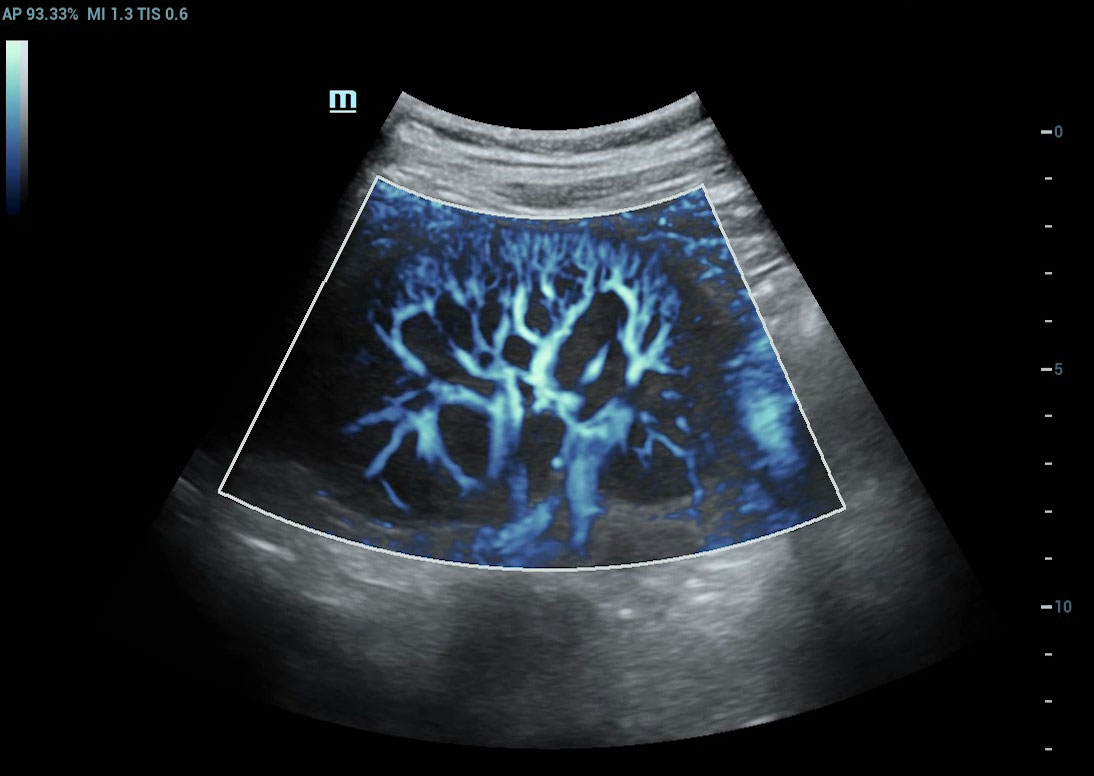

Ultra Micro Angiography (UMA)

UMA migliora la sicurezza diagnostica ampliando la visibilitĂ dei flussi sanguigni fino al livello dei vasi piĂč piccoli, con una sensibilitĂ e una risoluzione superiori.

Rene sUMA

Rene PUMA